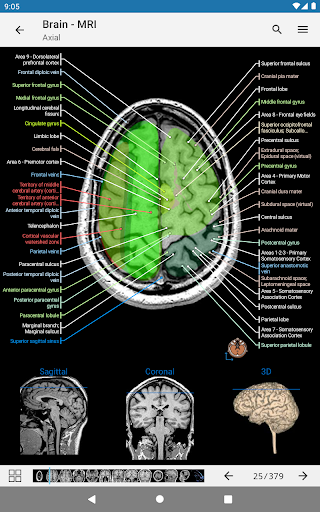

* تحسين عرض التفاصيل للأجزاء التشريحية لتسهيل التعرف عليها في صور الوحدات الحالية والوحدات الأخرى.

* تقليل حجم التطبيق واستهلاك البيانات من خلال تدفق الصور الطبية والرسوم التوضيحية

رسم توضيحي موجود الآن على كل صورة ويمثل الاتجاه الحالي للجسم

- عرض التشريحية يعرض الآن المزيد من التسميات